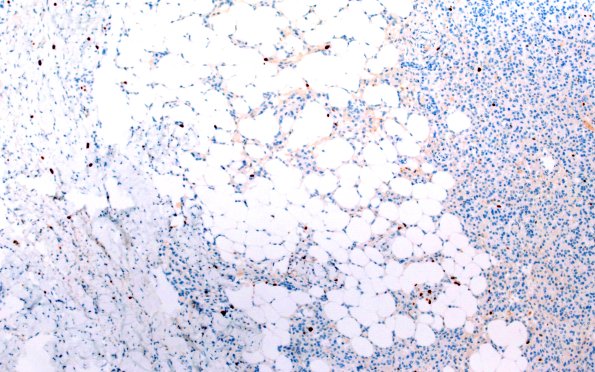

17F1 Meningioma, lipidized (Case 17) Ki67 10X

17F1,2 Ki-67 proliferation index is low, estimated up to 1.8% (Ki67 IHC).